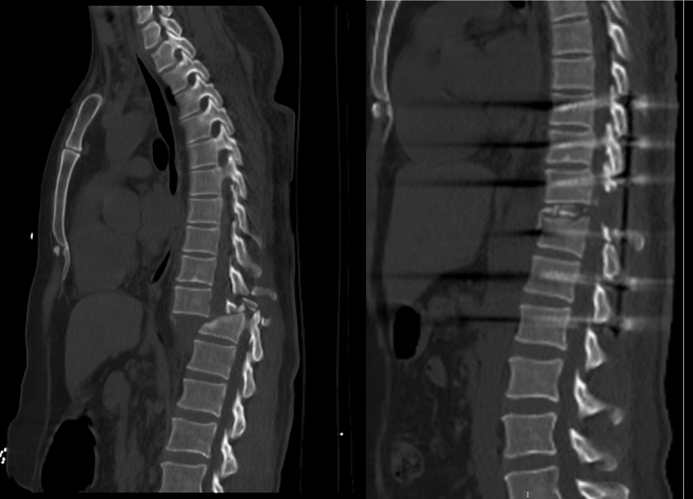

治疗前后对比图。

到达急诊科时,云浮市人民医院创伤中心已启动应急响应机制,集结了脊柱骨科、重症监护室、麻醉手术室、综合介入科、医学影像科、输血科、检验科等多学科骨干力量,并组建急救抢救小组。面对患者情况,团队首先致力于稳定其生命体征,在完成必要的紧急处理后,通过CT检查确认患者脊柱骨折脱位且神经完全性损伤,还出现大小便失禁等严重情况,这意味着患者的脊髓功能受到了严重影响。

令人欣慰的是,手术过程中患者并未出现大出血等意外情况,整体进展顺利。术后,患者被送入重症监护室进行密切监测,情况稳定后已转回骨科病房。近期CT检查显示,患者的脊柱已实现良好复位。